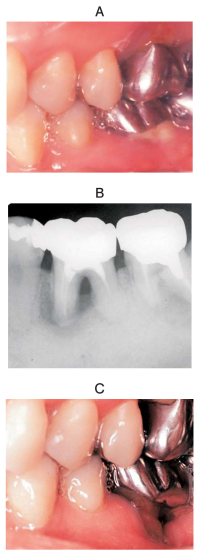

47 歳の女性。下顎左側第一大臼歯部歯肉の違和感を主訴として来院した。歯周基本治療後の再評価の結果、歯周外科治療を行うこととした。初診時の口腔内写真、エックス線画像及び再評価時の口腔内写真を別に示す。

術式選択にあたり、最も参考とするのはどれか。1つ選べ。

e. ファーケーションプローブによる検査結果